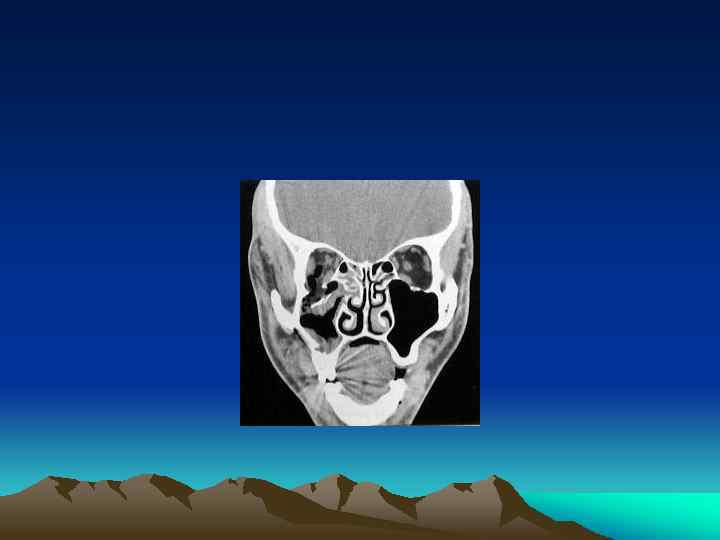

Facial Plain Films Ø Largely been replaced by computer tomography (except for the mandible) Plain Film Mandible Series and Panorex Computed Tomography (CT) Ø Most informative radiographic exam fro head and neck Trauma Ø Axial and coronal facial CT with bone and soft tissue window, 2 -3 mm sections

INTRODUCTION Ø Ø Ø Orbital Bones Optic Canal& Orbital Fissures Contents Sign& Symptoms

TYPES Ø Pure Ø Impure

Management Ø Indication for Surgical Intervention Ø Contraindications for Surgical Intervention: hyphema, retinal tear, globe perforation, only seeing eye sinusitis, frozen globe Ø Ophthalmological Evaluation Ø Timing : 1 week Ø Technique